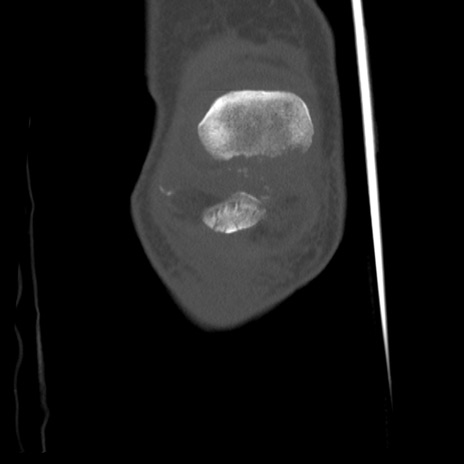

症例28 右膝関節CT(冠状断像)

右膝関節CT

横断像